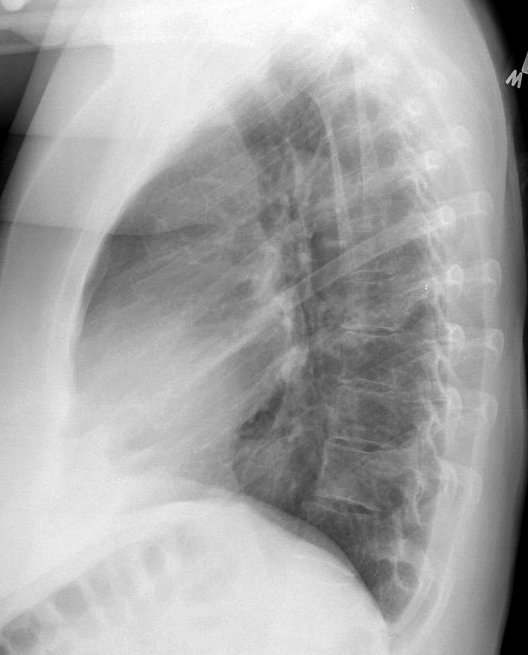

Hiatus Hernia

Case 6 Lat